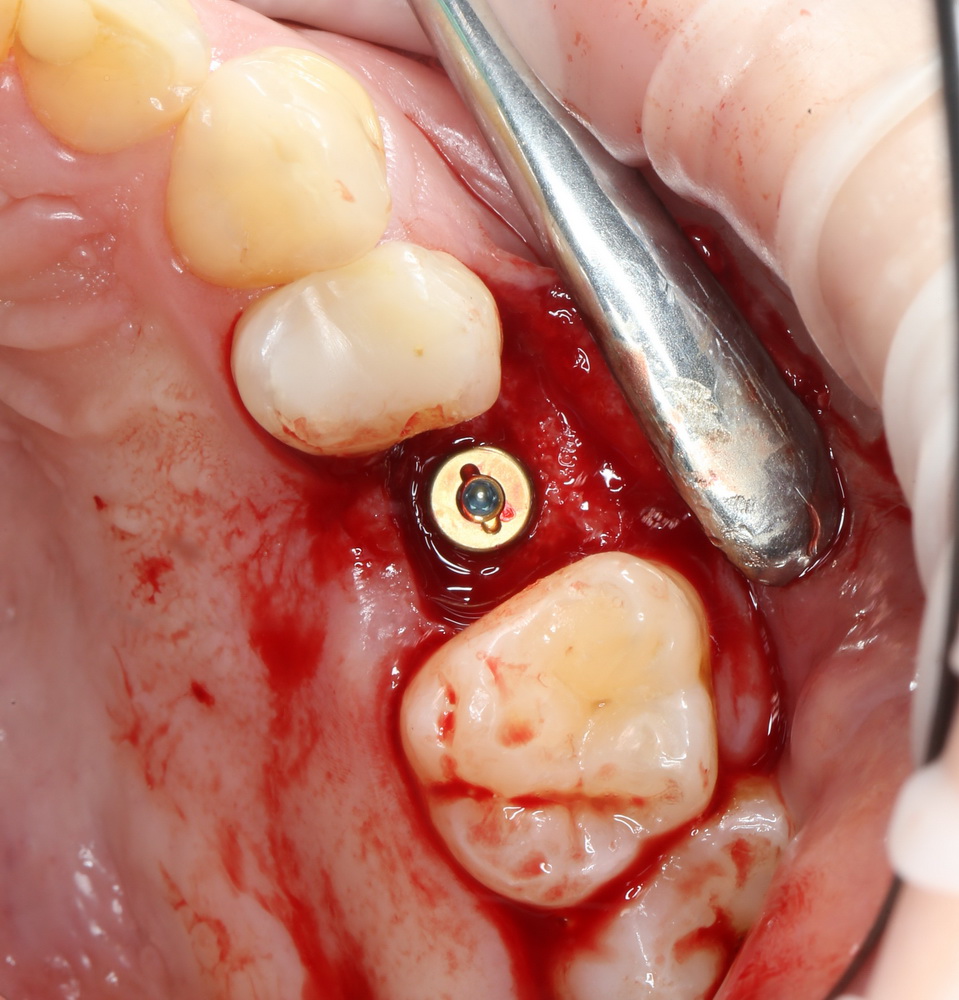

Ничего не стоит поставить имплантат в такие объемы кости и при таком качестве слизистой оболочки:

Обратите внимание: даже там, где отсутствовала вестибулярная стенка лунки, восстановилась костная ткань:

Теперь мы просто ставим имплантат. Без синуслифтинга. И без проблем со стабилизацией:

А качество и объем слизистой оболочки настолько хороши, что можно сразу поставить формирователь десны: